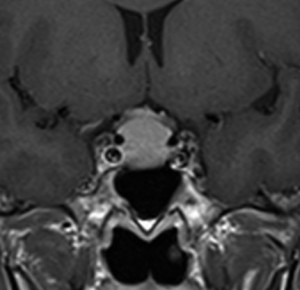

鞍結節部髄膜腫 tuberculum sellae meningioma

鞍結節髄膜腫は小さくてもとても面倒です。両側の内頚動脈の内側から周囲にからんでくることと,視神経管の中に腫瘍が浸潤して行くことです。左右の視神経,左右の内頚動脈,鞍隔膜,下垂体柄という構造物に囲まれているので摘出しづらいものです。

この図のように,視神経(黄色)は,骨(青色)で形成される視神経管の中を走行して頭蓋内へ入ります。視神経管は骨ですから,この狭い管の中に腫瘍が入ると視神経が腫瘍の圧迫でつぶれてしまって,視力障害を出しやすいです。

鞍結節髄膜腫(赤色)はこの視神経管の中に浸潤して伸びていく性質を有しています。ですから,視神経管の骨を削って,視神経管の中に潜り込んでいる腫瘍を根こそぎ摘出しないと,再発する可能性が高いです。

視神経管内部には,下内側面からの浸潤が多いので,経鼻手術で外しやすい部位とも言えます。大きな腫瘍の場合は,視神経は視神経管から出た直後で,上方やや前方向きに折れ曲がっています。